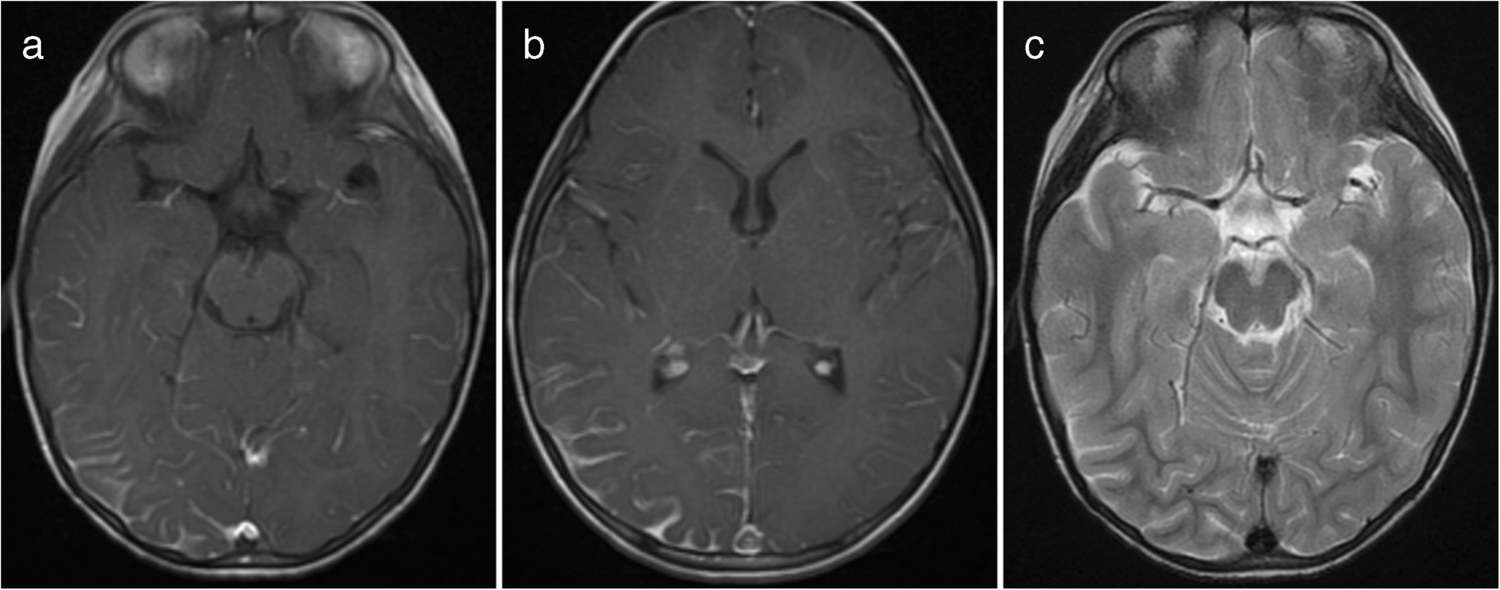

A cortical encephalitis pattern was identified in three patients, and an aseptic meningitis pattern was seen in six patients (Figs. 4 and 5, respectively). Tumefactive demyelinating lesions were observed in three cases. These lesions were large (> 2 cm) and unifocal, resembling either neoplastic processes or localized abscesses (Fig. 6). The lesions were located in the periventricular white matter, thalamus, and subcortical white matter/cortex, respectively. Unlike typical tumors, these lesions did not demonstrate mass effect. A cerebellitis/brainstem encephalitis pattern was found in two patients (Fig. 7). One patient exhibited non-enhancing lesions in the cerebellar white matter and midbrain, while the other had poorly defined cerebellar cortical lesions with curvilinear enhancement. Among the miscellaneous patterns, one patient showed a leukodystrophy-like presentation (Fig. 8a), and another exhibited an MS-like pattern (Fig. 8b–d).

Fig. 6

Magnetic resonance images illustrate myelin oligodendrocyte glycoprotein antibody-associated diseases with a tumefactive demyelination pattern. a, b Axial fluid-attenuated inversion recovery (a) and post-contrast T1-weighted (b) images from a 16-year-old girl show a large, focal hyperintense lesion in the right periventricular white matter with subtle linear enhancement. No notable mass effect is present. c, d Axial T2 (c) and T1 post-contrast (d) images from a 10-year-old girl with seizure demonstrate a focal cortical/subcortical lesion in the left frontal lobe. The lesion displays curvilinear, incomplete ring enhancement (arrow in d). This lesion was initially misdiagnosed as a small cortical abscess

Fig. 7

Magnetic resonance images illustrate myelin oligodendrocyte glycoprotein antibody-associated diseases with a cerebellitis/brainstem encephalitis pattern. a, b Axial T2-weighted images obtained at the fourth ventricle level (a) and the midbrain level (b) in a 5-year-old boy with dizziness show bilateral lesions in the cerebellar white matter (arrows in a) and midbrain (arrows in b). c, d Axial T2-weighted (c) and post-contrast T1-weighted (d) images in a 12-year-old girl with isolated cerebellitis show an ill-defined hyperintense lesion (arrow in c) in the right cerebellar cortex with curvilinear enhancement (arrow in d)